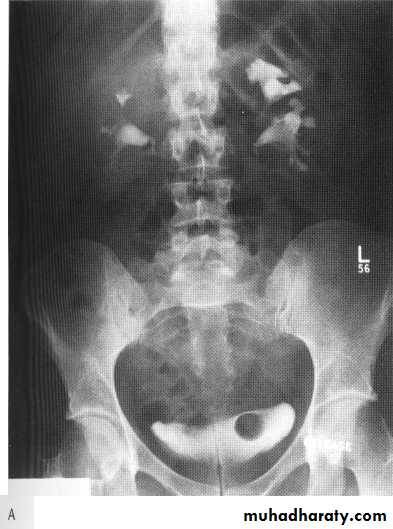

small kidney

unilateral small kidneyin all these cases chronic unilateral disease is associated with compensatory hypertrophy of contralateral kidney

1. due to post obstruction atrophy(with dilated collecting system)

2. Ischemia due to renal artery stenosis

3. radiation nephritis (2300 rad )

4. end result renal infarction (renal artery vein thrombosis or renal artery embolism )

5. in congenital hypoplasia